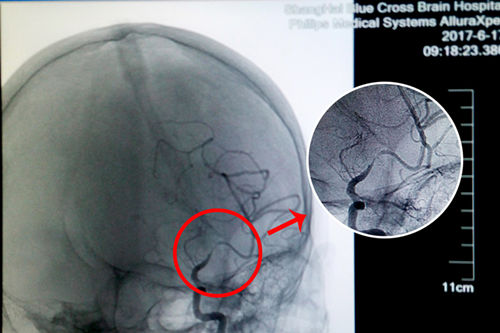

更为严重的是,入院后在DSA检查中还发现患者左侧大脑中动脉已经出现70%以上的狭窄,非常危险。李振并主任解释,脑血管狭窄是造成缺血性脑血管病的一个重要病因和危险因素,脑血管狭窄使得经过脑血管的血液减少,脑细胞就会缺血死亡。在临床上,脑血管狭窄程度在50%以下通过药物治疗,在50%-70%之间就要进行通过血管介入进行腔内血管成形术(球囊扩张支架置入术),而70%以上必须马上通过血管介入进行腔内血管成形术(球囊扩张支架置入术),否则一旦脑细胞因缺血大量死亡,患者会有性命之忧。

术前DSA影像显示,患者大脑中动脉血管70%以上狭窄